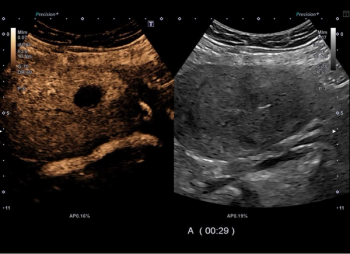

A prospective observational study in the Journal of Ultrasound in Medicine has concluded that for pretreatment evaluation of uterine fibroids (UF), transabdominal contrast-enhanced ultrasound (CEUS) represents a viable alternative to traditional contrast-enhanced magnetic resonance imaging (MRI).